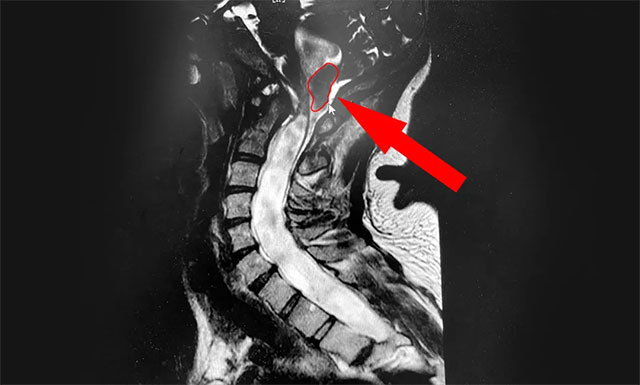

▲ MRI示患者小腦扁桃體下疝畸形

侯增欣主任耐心詢問了患者病史,并開展了有針對(duì)性的檢查。小潘的頸椎核磁檢查報(bào)告很快出來了,從影像上看,患者的頸6/7椎間盤確實(shí)稍有突出,但程度并不嚴(yán)重。而導(dǎo)致患者癥狀不斷加重的“元兇”同時(shí)現(xiàn)形:小腦扁桃體延長成楔形進(jìn)入了枕骨大孔及頸椎管,頸髓受壓水腫改變,頸髓及上端胸髓內(nèi)見條狀異常信號(hào),提示為“Chiari畸形伴脊髓空洞癥”。